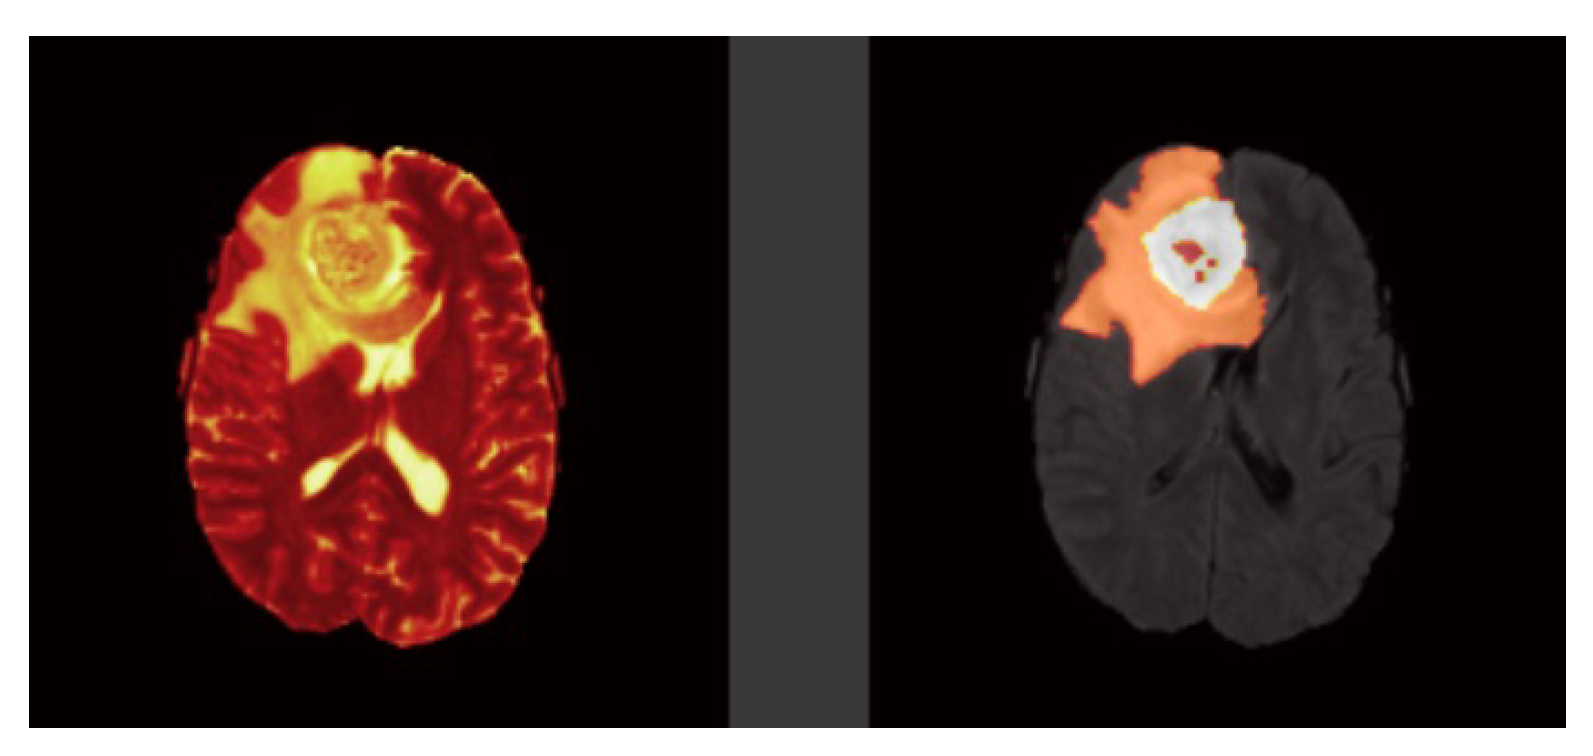

Figure 2.

Brain tumor modalities. Left image: T2-weighted and Right image: Ground Truth.

Tl-weighted is basically used to distinguish between healthy and diseased tissues, and these scans offer a distinction between gray and white matter Figure 1. T2-weighted are well matched to brain disorders in which water accumulates within brain tissues due to the vulnerability of this modality to water content Figure 2. This modality determines the area of the edema, resulting in the generation of a bright signal on the image. Colorless fluid found in the spinal cord and brain known as cerebrospinal fluid (CSF) can be separated effectively using T1 and T2-weighted images. In T2-weighted images this CSF looks bright, and in T1-weighted images look dark. T1-weighted MRI with gadolinium contrast enhancement (T1-Gd) is the fourth type of MRI sequence. In this modality, an accumulated contrast agent, such as gadolinium ions, is used in the active cell area of the tumor tissues to produce a bright signal that facilitates the demarcation of the tumor boundaries. Since necrotic cells do not associate with contrast agents, they are segregated as a hypo-intense part of the center of the tumor, and this promotes the segmentation of the hypo-intense part of the active cell zone. FLAIR, with the exception of its acquisition protocol, is identical to T2-weighted images. Here the suppression of the water molecule is achieved, which in turn helps to discriminate between the edema and the CSF. FLAIR has the capacity to block water signals, and the hypertensive periventricular lesion is easily visible.